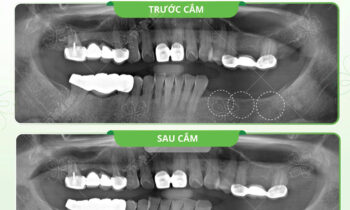

Hoàn thành 1 quá trình niềng răng đổi lại kết quả như này thật sự xứng đáng đúng không cả nhà???? ❌Bạn sẽ thấy khuôn mặt mình mất cân đối khi gặp tình trạng răng móm, hô, lệch,…khiến bạn cảm thấy tự ti khi cười với người đối diện. ????Tuy nhiên, nhờ vào phương pháp…